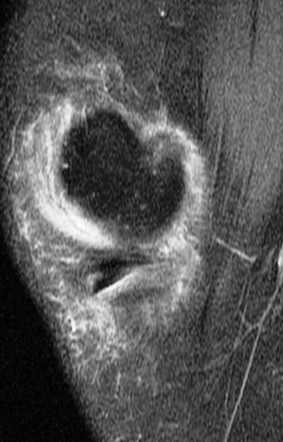

Figure 1 for case Unstable flap tear medial meniscus

Figure 1

With a displaced flap into the coronary recess. No sign of patellar dislocation. PD fat sat shows the inflammatory change that often accompanies and unstable tear. Displacement of meniscal tissue=instability.

Unstable flap tear medial meniscus